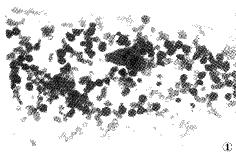

3.骨髓檢查

骨髓塗片可見到噬血現象,早期噬血現象不明顯,多次骨髓塗片有助於發現噬血現象。此外還應行骨髓活檢術,進行骨髓病理檢查以除外血液/淋巴系統腫瘤。